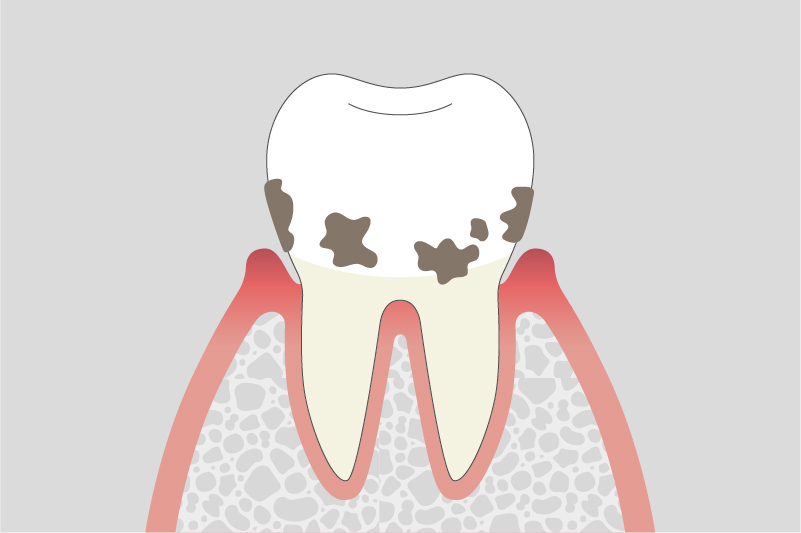

03.

中等度歯周炎

歯を支える骨(歯槽骨)が徐々に溶け始め、歯がぐらつくことがあります。また、噛んだ時に違和感や痛みを感じることがあります。